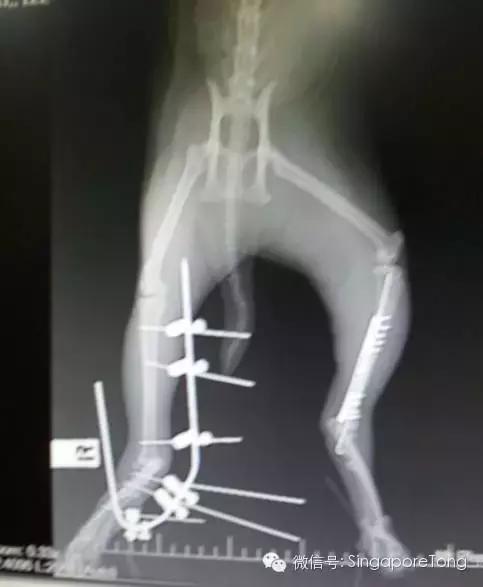

猫咪的腿被活生生的打断!